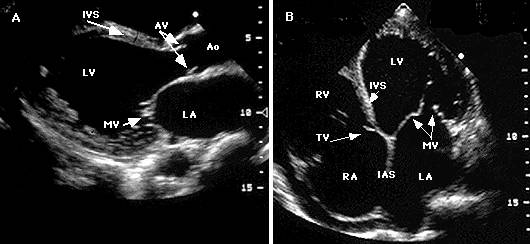

Ecocardiografia

Confirma diagnosticul de CMH, cuantifica elementele morfologice - distributia hipertrofiei, functionale - hipercontractilitatea VS si hemodinamice - gradientul intraventricular.

Caracterele ecocardiografice sunt :

Examenul Doppler evidentiaza prezenta gradientului, a insuficientei mitrale si anomaliile functiei diastolice.